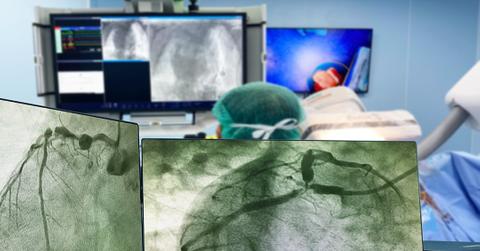

A window into a widowmaker

The results made the scope of Malin’s heart problem stunningly clear: He had a 99% blockage of his left anterior descending (LAD) artery. A heart attack originating in the LAD is sometimes called a “widowmaker” because the artery plays such a key role in supplying blood to the heart. The interventional cardiology team fixed the problem on the spot, inserting a mesh stent in Malin’s LAD to prop it open. Six hours later, Malin went home, healthy, grateful and ready to adopt the medications and lifestyle changes his doctors advised.

“I’ve got pictures of my heart that clearly show the before and the after,” says Malin. “It’s very alarming how close I was to a tragedy.”

Coronary angiogram

Why you might need it: You’re having new or worsening symptoms suggestive of heart disease or received abnormal test results that require further investigation.

How it works: A flexible tube called a catheter is inserted into an artery in your wrist or groin and threaded to the coronary arteries in your heart. Dye is injected to make it easier to get a detailed view of blood vessels on an X-ray image called an angiogram. You’ll likely get a light sedative to help you relax. As with Malin, results might lead to the immediate placement of a stent; a short hospital stay may be required.

What it shows: It can detect restricted blood flow to the heart.